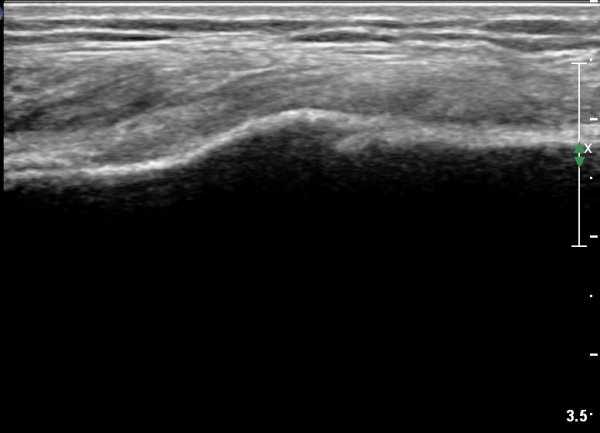

[¹«¸­] °æ°ñ ÇǷΰñÀý ÃÊÀ½ÆÄ¼Ò°ß(sonographic findings of stress fracture of tibia)

¿ìÃø ¹ß¸ñ°ú ¾Æ·§´Ù¸® ÅëÁõ(±â°£ 2ÁÖ)

±º´ë¿¡ ÀÔ´ëÇÏ¿© ÈÆ·ÃÀ» ¹ÞÀº º´·ÂÀÌ Àִ ȯÀÚ´Â ¾à 2ÁÖ ÀüºÎÅÍ ¹ß¸ñ ºÎÀ§ÀÇ ÅëÁõÀÌ ÀÖ´ø Áß

ÃÖ±Ù¿¡´Â ¹ß¸ñ À§ ¾Æ·§´Ù¸®¿¡ ÅëÁõÀÌ ¹ß»ýÇÏ°í ½ÉÇÏ°Ô °ÉÀ¸¸é ½ÉÇØÁö´Â ¾ç»óÀÓ

¾Æ·§´Ù¸® Áß°£ ºÎÀ§¿¡ °æ¹ÌÇÑ ¿¬ºÎÁ¶Á÷ ºÎÁ¾ÀÌ °üÂûµÇ°í ¾à°£ÀÇ ±¹¼ÒÀû ¾ÐÅëÀ» º¸ÀÓ.

ÃÊÀ½ÆÄ °Ë»ç

¹Ì¼¼ÇÏ°Ô ¿¬ºÎÁ¶Á÷ ºÎÁ¾°ú °¡°ñ Çü¼ºÀÌ °üÂûµÊ.

Bilateral stress fracture of the tibia diagnosed by ultrasound. A case report

https://www.ncbi.nlm.nih.gov/pmc/articles/PMC3558228/pdf/main.pdf